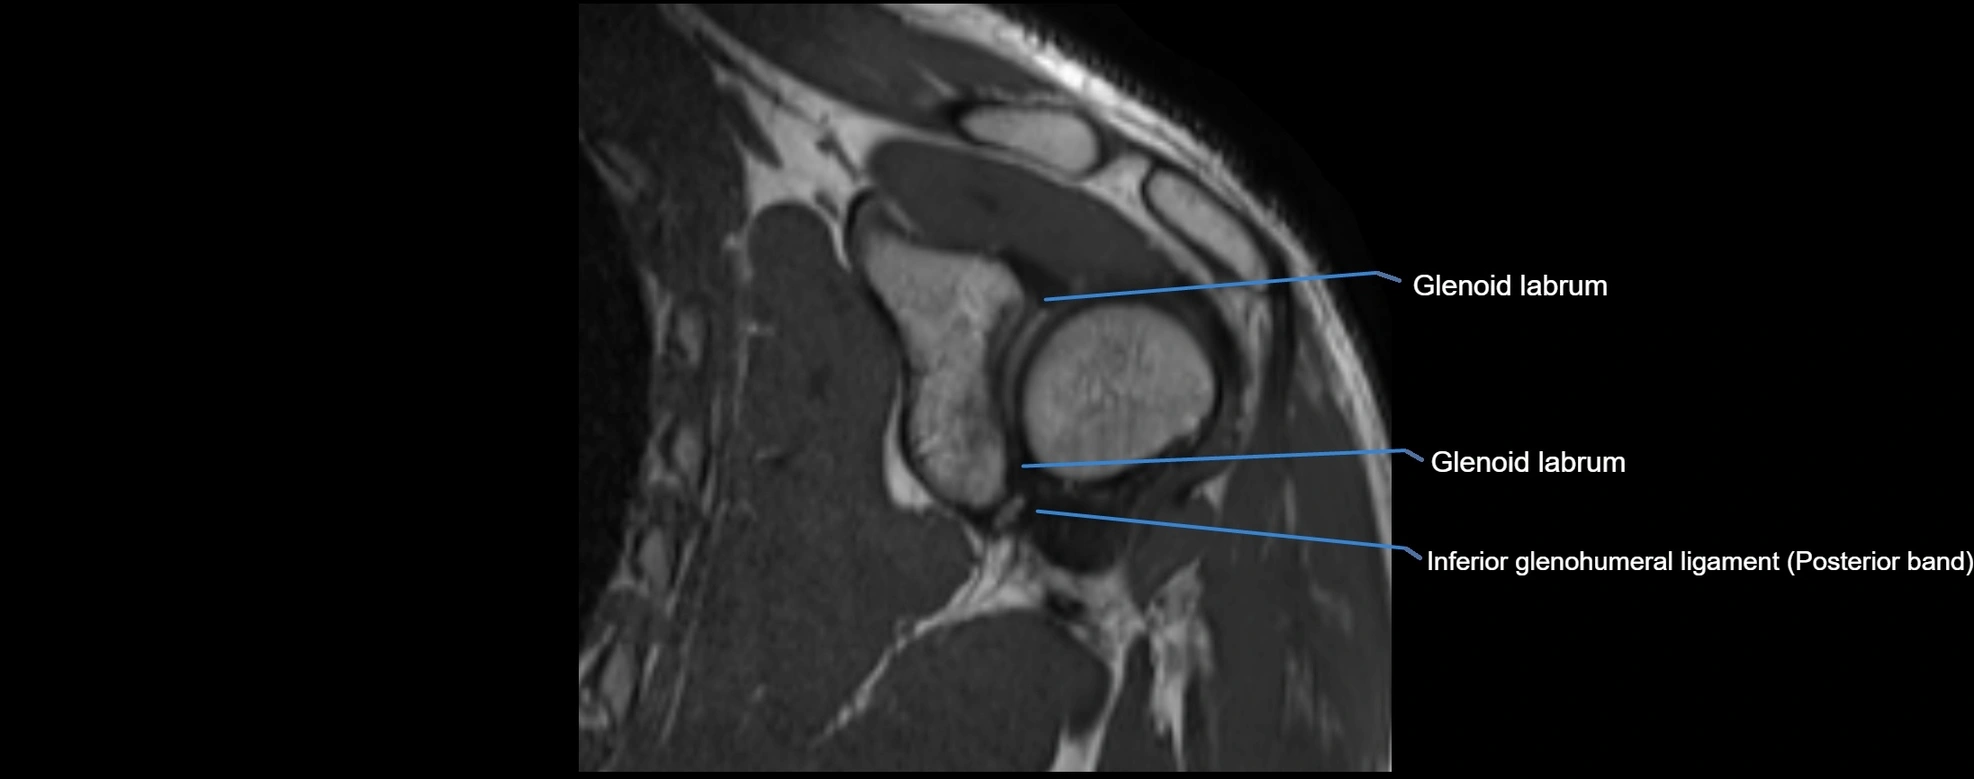

MRI images

image